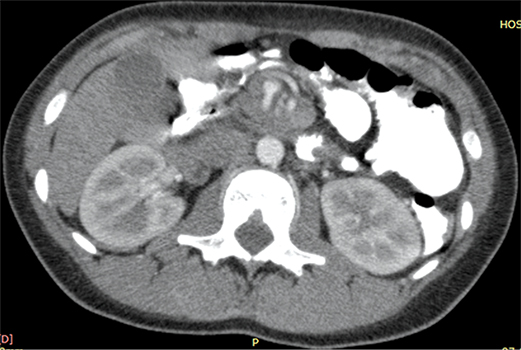

Paciente de sexo femenino, de 18 años, que concurre al servicio de emergencias presentando dolor epigástrico agudo e intermitente de 6 horas de evolución. Semiológicamente el dolor empeora con la ingesta y se asocia con náuseas y vómitos de tipo biliosos. Al examen físico, llama la atención la marcada distensión abdominal. Se solicitan como estudios complementarios una ecografía abdominal (Figura 1), un tránsito de intestino delgado con contraste hidrosoluble (Figura 2) y una tomografía computada con contraste oral y endovenoso (Figura 3).